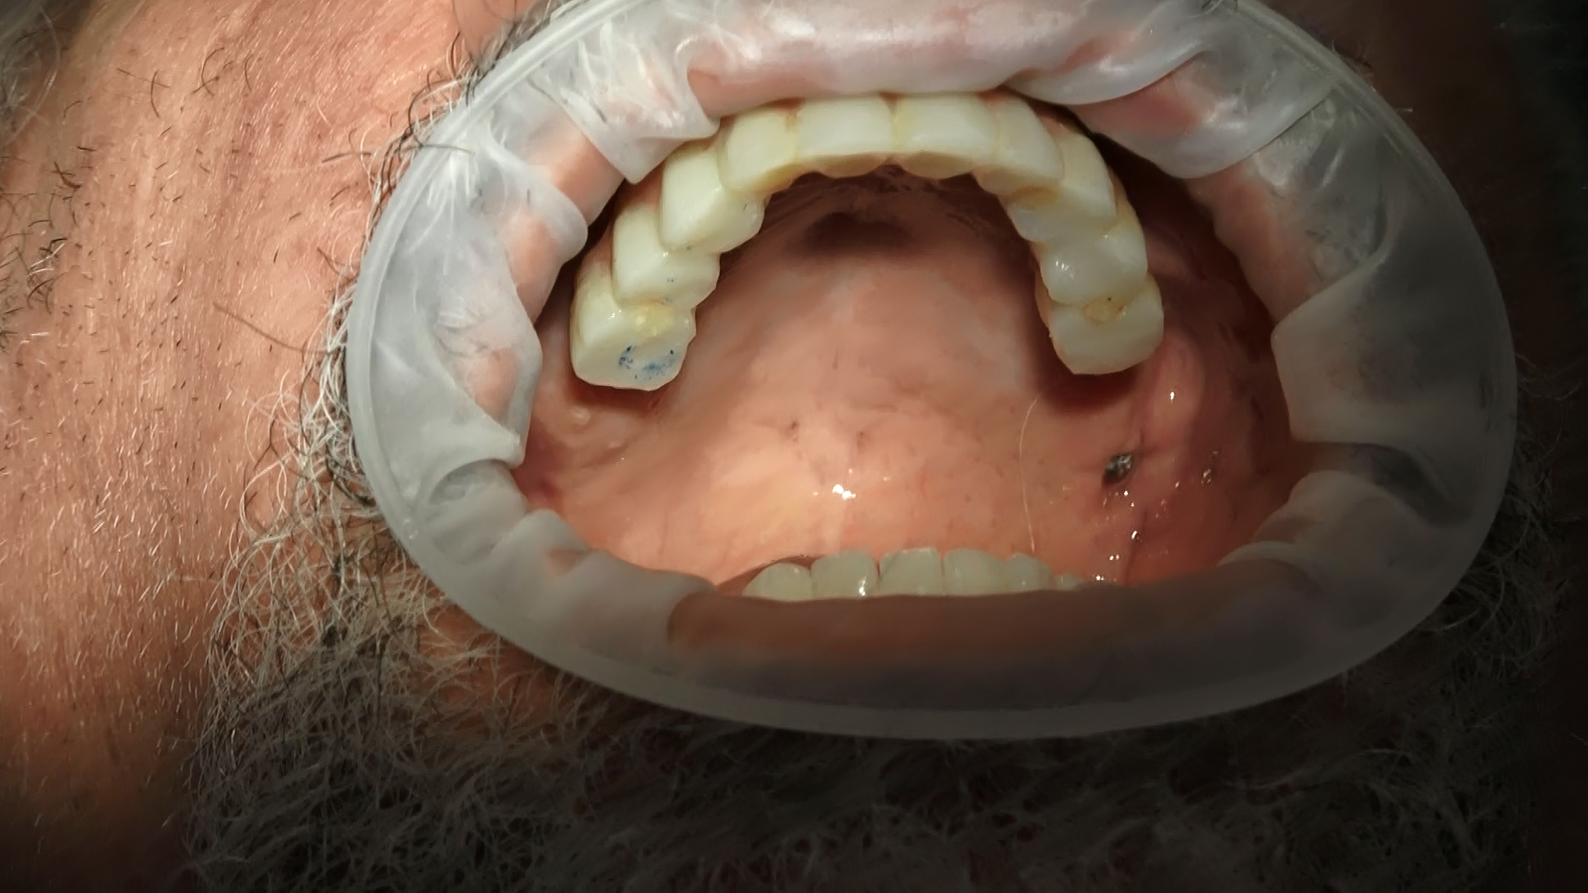

Segue cambio protesi da fissa provvisoria a fissa definitiva solo sotto, la parte superiore deve essere ancora sostituita con la protesi definitiva.

Secondo caso clinico paziente della Sardegna 30 anni di dentiera e in un ora e trenta passa da 30 anni di protesi mobile a dentatura fissa a carico immediato. Segue il momento del cambio protesi dopo 6 mesi da fissa provvisoria a fissa definitiva circolare 14 denti ceramica zirconio con una bellissima estetica per la piena soddisfazione della nostra paziente.

Dopo circa 6 mesi, una volta completata la fase di guarigione, viene realizzata e posizionata una protesi definitiva. Questa protesi può includere anche impianti pterigoidei per una maggiore stabilità e supporto. La protesi definitiva permette al paziente di avere un sorriso completo e funzionale, ripristinando la sua capacità di masticare e parlare correttamente.